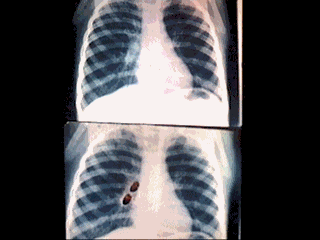

RX.QUE

CORESPONDE A UN PACIENTE QUE PRESENTO 40 DIAS DE CRISIS DE TOS TIPO

TOSFERINA.OBSERVANDO EN LA RX.ENGROSAMIENTO PERIHILIAR DERECHO.SE

REALIZA BRONCOSOPIA Y SE ENCUENTRA 2 SEMILLAS DE FRUTA ALOJADO EN

BRONQUIO PRINCIPAL DERECHO. FORTEEN DAY COUGH EVOLUTION CHILD.DON'T

LOOK FOREIGN BODY RX..BRONCOSCPY LOOK F.B.